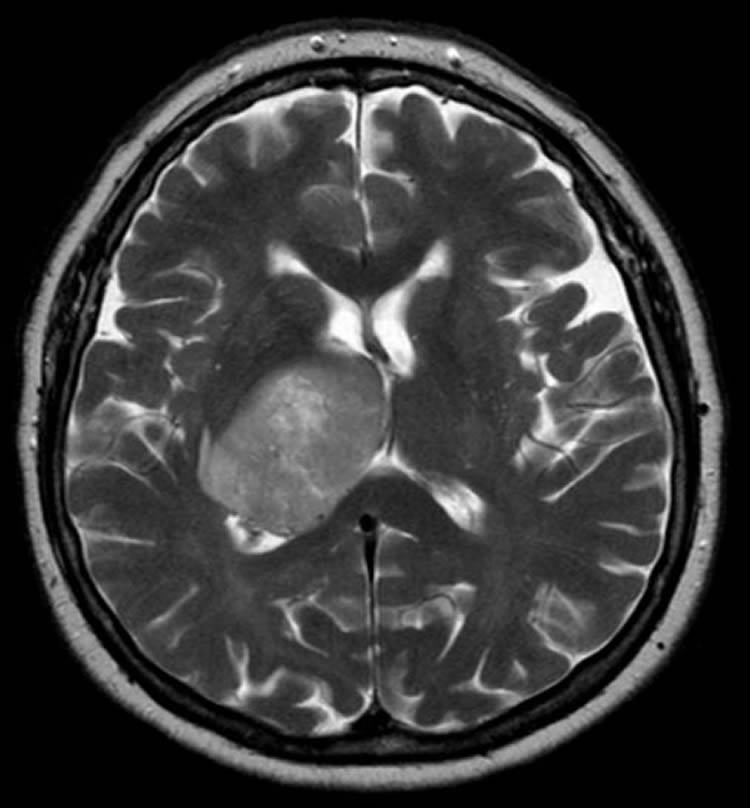

Image Source: The image is credited Hellerhoff and is licensed Creative Commons Attribution-Share Alike 3.0 Unported